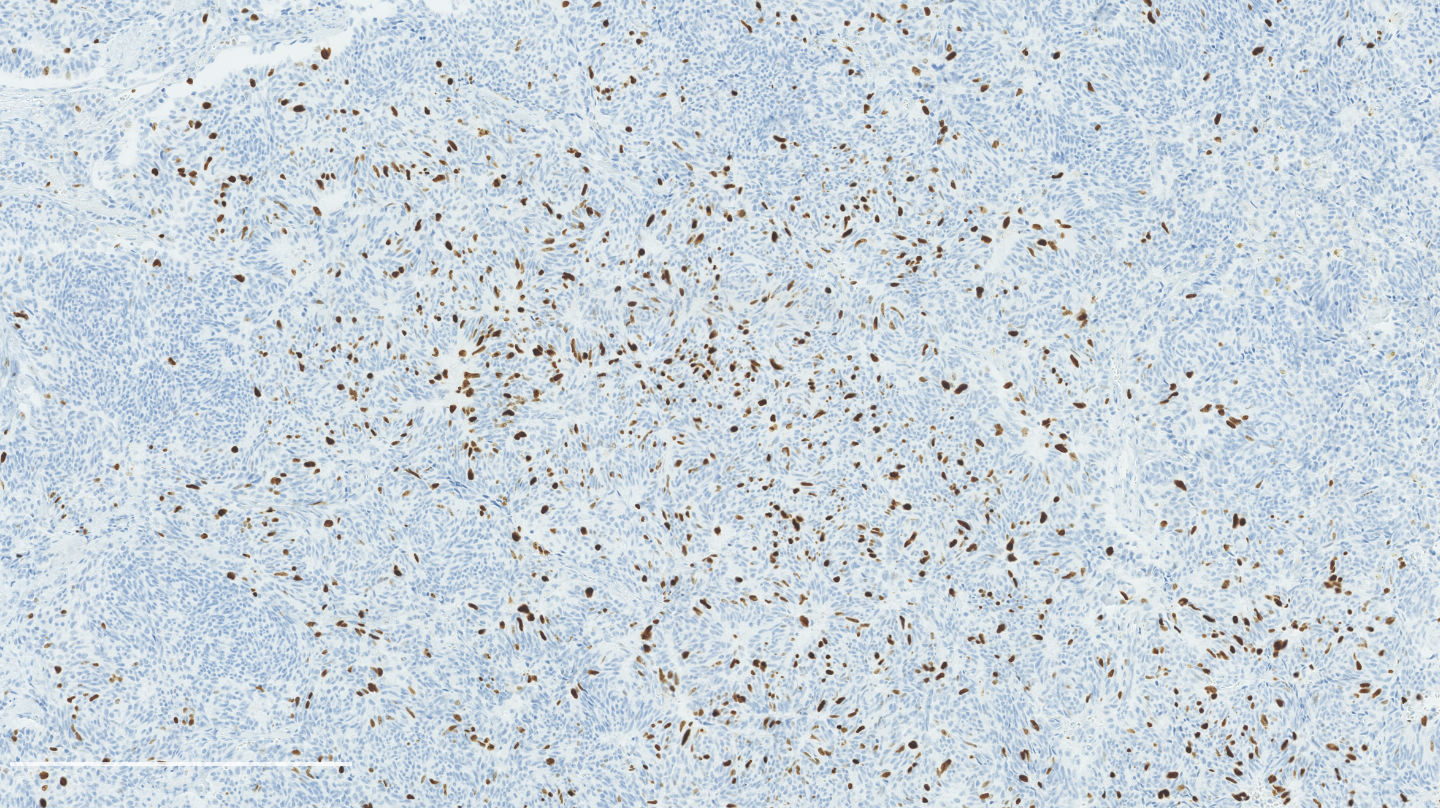

Microscopic (histologic) description

- Diagnostic criteria:

- Neuroendocrine morphology with 2 - 10 mitoses per 2 mm² or presence of necrosis

- Necrosis can be in large zones but is usually punctate

- Mitotic rate should be counted in the area with the highest proliferation rate (hot spot)

- If mitotic rate is near cutoffs, assessment should be made on three sets of 2 mm² and their mean should count as the final mitotic rate

- Neuroendocrine morphology with 2 - 10 mitoses per 2 mm² or presence of necrosis

- Neuroendocrine histologic patterns similar to typical carcinoids: organoid, trabecular, rosette formation, papillary, pseudoglandular, follicular

- Tumor cells are as typical carcinoid: uniform with a polygonal shape, round to oval nuclei with salt and pepper chromatin and inconspicuous nucleoli, along with moderate to abundant eosinophilic cytoplasm

- Greater pleomorphism than for typical carcinoid is common (Arch Pathol Lab Med 2010;134:1628)

- Spindle cells and clear cell features can be seen

- Stroma is fine and highly vascularized; hyalinization, cartilage or bone formation are possible

Microscopic (histologic) images

Contributed by Philippe Joubert, M.D., Ph.D.

Positive stains

- Chromogranin, synaptophysin, CD56: diffusely and strongly positive; can be negative in a small number of atypical carcinoids (Hum Pathol 2000;31:1255)

- Ki67: should not be used as a diagnostic criterion (J Thorac Oncol 2019;14:377)

- Mostly useful to differentiate lung carcinoids from high grade neuroendocrine carcinomas, in particular in small biopsies or cytology samples (Arch Pathol Lab Med 2018;142:947, J Thorac Oncol 2014;9:273)

- Usually < 20% but a > 30% cutoff has been proposed (Virchows Arch 2017;470:153, J Thorac Oncol 2014;9:273)

- Reported to be higher than typical carcinoid (2 - 5% versus 9 - 18%) but not proven to be a reliable marker